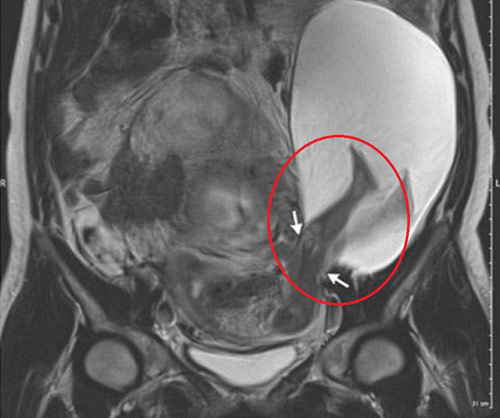

"Một người phụ nữ 33 tuổi đi siêu âm ở tuần 22 thai kỳ và được phát hiện có một túi nước nhỏ như một phần của túi ối bị thoát ra khỏi thành tử cung. Chụp cộng hưởng từ cho thấy túi nước này có đường kính khoảng 2,5cm và chứa 2 chân của thai nhi", bác sĩ sản phụ khoa Pierre-Emanuel Bouet chia sẻ trên tạp chí Y học The New England.

Hình ảnh siêu âm cho thấy chân thai nhi nằm ở ngoài thành tử cung. Ảnh: The New England Journal of Medicine |

Nên đọcĐến tuần thứ 30, hình siêu âm cho thấy vết rách đã lớn hơn và thai nhi ngày càng ra ngoài tử cung.